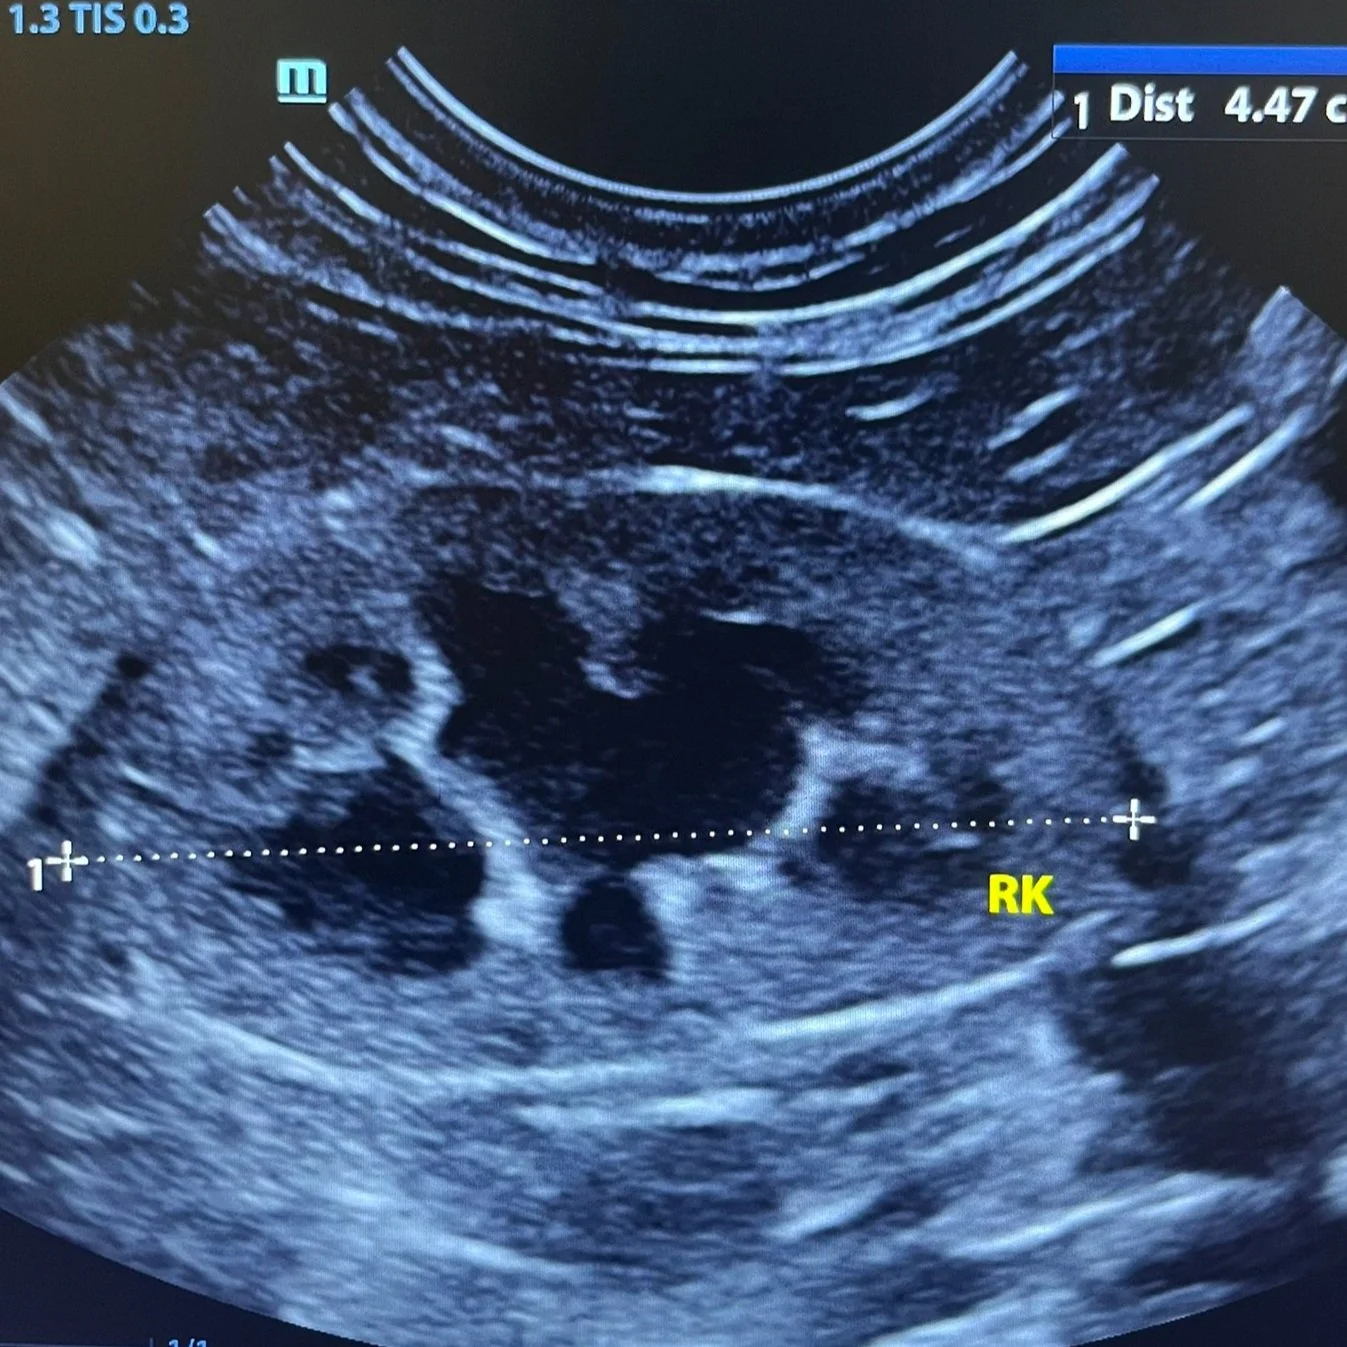

During a veterinary ultrasound, we use a small handheld probe that glides smoothly over your pet's fur and skin. The probe emits sound waves that bounce off internal organs, allowing us to create live, detailed images of your pet's internal structures on a monitor. This allows us to examine the abdomen, heart, or other areas with precision, capturing important information without causing any discomfort to your pet.